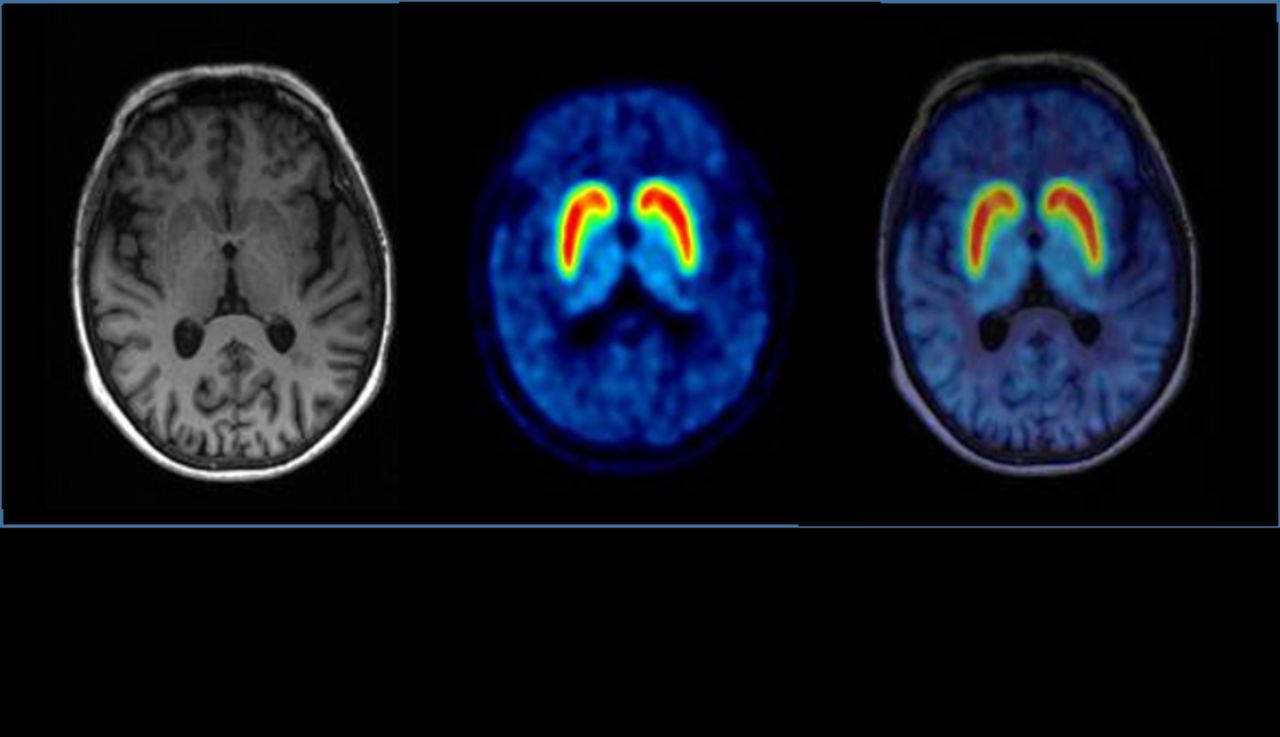

Today, modern medicine is undergoing another major transformation—and nuclear medicine and molecular imaging are on its leading edge, probing deep inside the body to reveal its inner workings.

Unlike conventional imaging studies that produce primarily structural pictures, nuclear medicine and molecular imaging visualize how the body is functioning and what’s happening at the cellular and molecular level. The evolution in diagnostic imaging—from producing anatomical pictures to imaging and measuring the body’s physiological processes—is critically important to all facets of medicine today, from diagnosing disease at its earliest stage and developing more effective therapies to personalizing medical treatment.